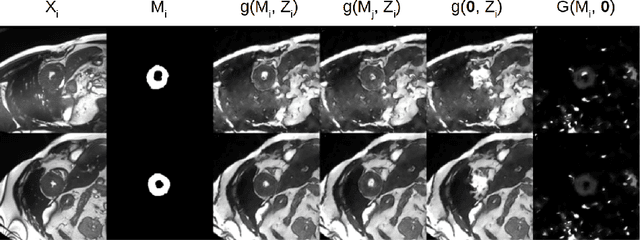

Abstract:Typically, a medical image offers spatial information on the anatomy (and pathology) modulated by imaging specific characteristics. Many imaging modalities including Magnetic Resonance Imaging (MRI) and Computed Tomography (CT) can be interpreted in this way. We can venture further and consider that a medical image naturally factors into some spatial factors depicting anatomy and factors that denote the imaging characteristics. Here, we explicitly learn this decomposed (factorised) representation of imaging data, focusing in particular on cardiac images. We propose Spatial Decomposition Network (SDNet), which factorises 2D medical images into spatial anatomical factors and non-spatial imaging factors. We demonstrate that this high-level representation is ideally suited for several medical image analysis tasks, such as semi-supervised segmentation, multi-task segmentation and regression, and image-to-image synthesis. Specifically, we show that our model can match the performance of fully supervised segmentation models, using only a fraction of the labelled images. Critically, we show that our factorised representation also benefits from supervision obtained either when we use auxiliary tasks to train the model in a multi-task setting (e.g. regressing to known cardiac indices), or when aggregating multimodal data from different sources (e.g. pooling together MRI and CT data). To explore the properties of the learned factorisation, we perform latent-space arithmetic and show that we can synthesise CT from MR and vice versa, by swapping the modality factors. We also demonstrate that the factor holding image specific information can be used to predict the input modality with high accuracy.